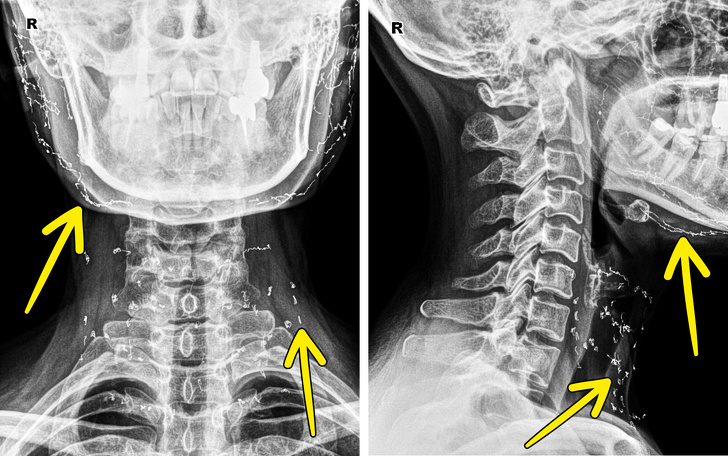

8. Рентгенівський знімок пацієнтки, яка пройшла процедуру підтяжки золотими нитками